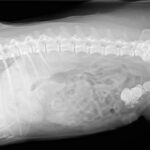

El principal problema de que nuestro perro sufra una picadura en su boca o laringe es que la inflamación obstruya sus vías y dificulte su respiración, con el consiguiente riesgo de que el perro muera asfixiado. Si esto ocurre, o si sospechamos que ha ocurrido porque apreciamos inflamación en su boca o garganta, debemos acudir con urgencia a un centro veterinario para que le atiendan y administren el tratamiento adecuado.

Normalmente se aplica mediante vía intravenosa una dosis de corticoides o antihistamínicos, siendo la metilprednisolona (Urbason®), el más indicado normalmente en estos casos. Lo mismo habrá que hacer en el caso de que nuestro perro presente síntomas como vómitos, diarreas, mucosas pálidas, debilidad, lo que puede ser indicativo de un shock anafiláctico.